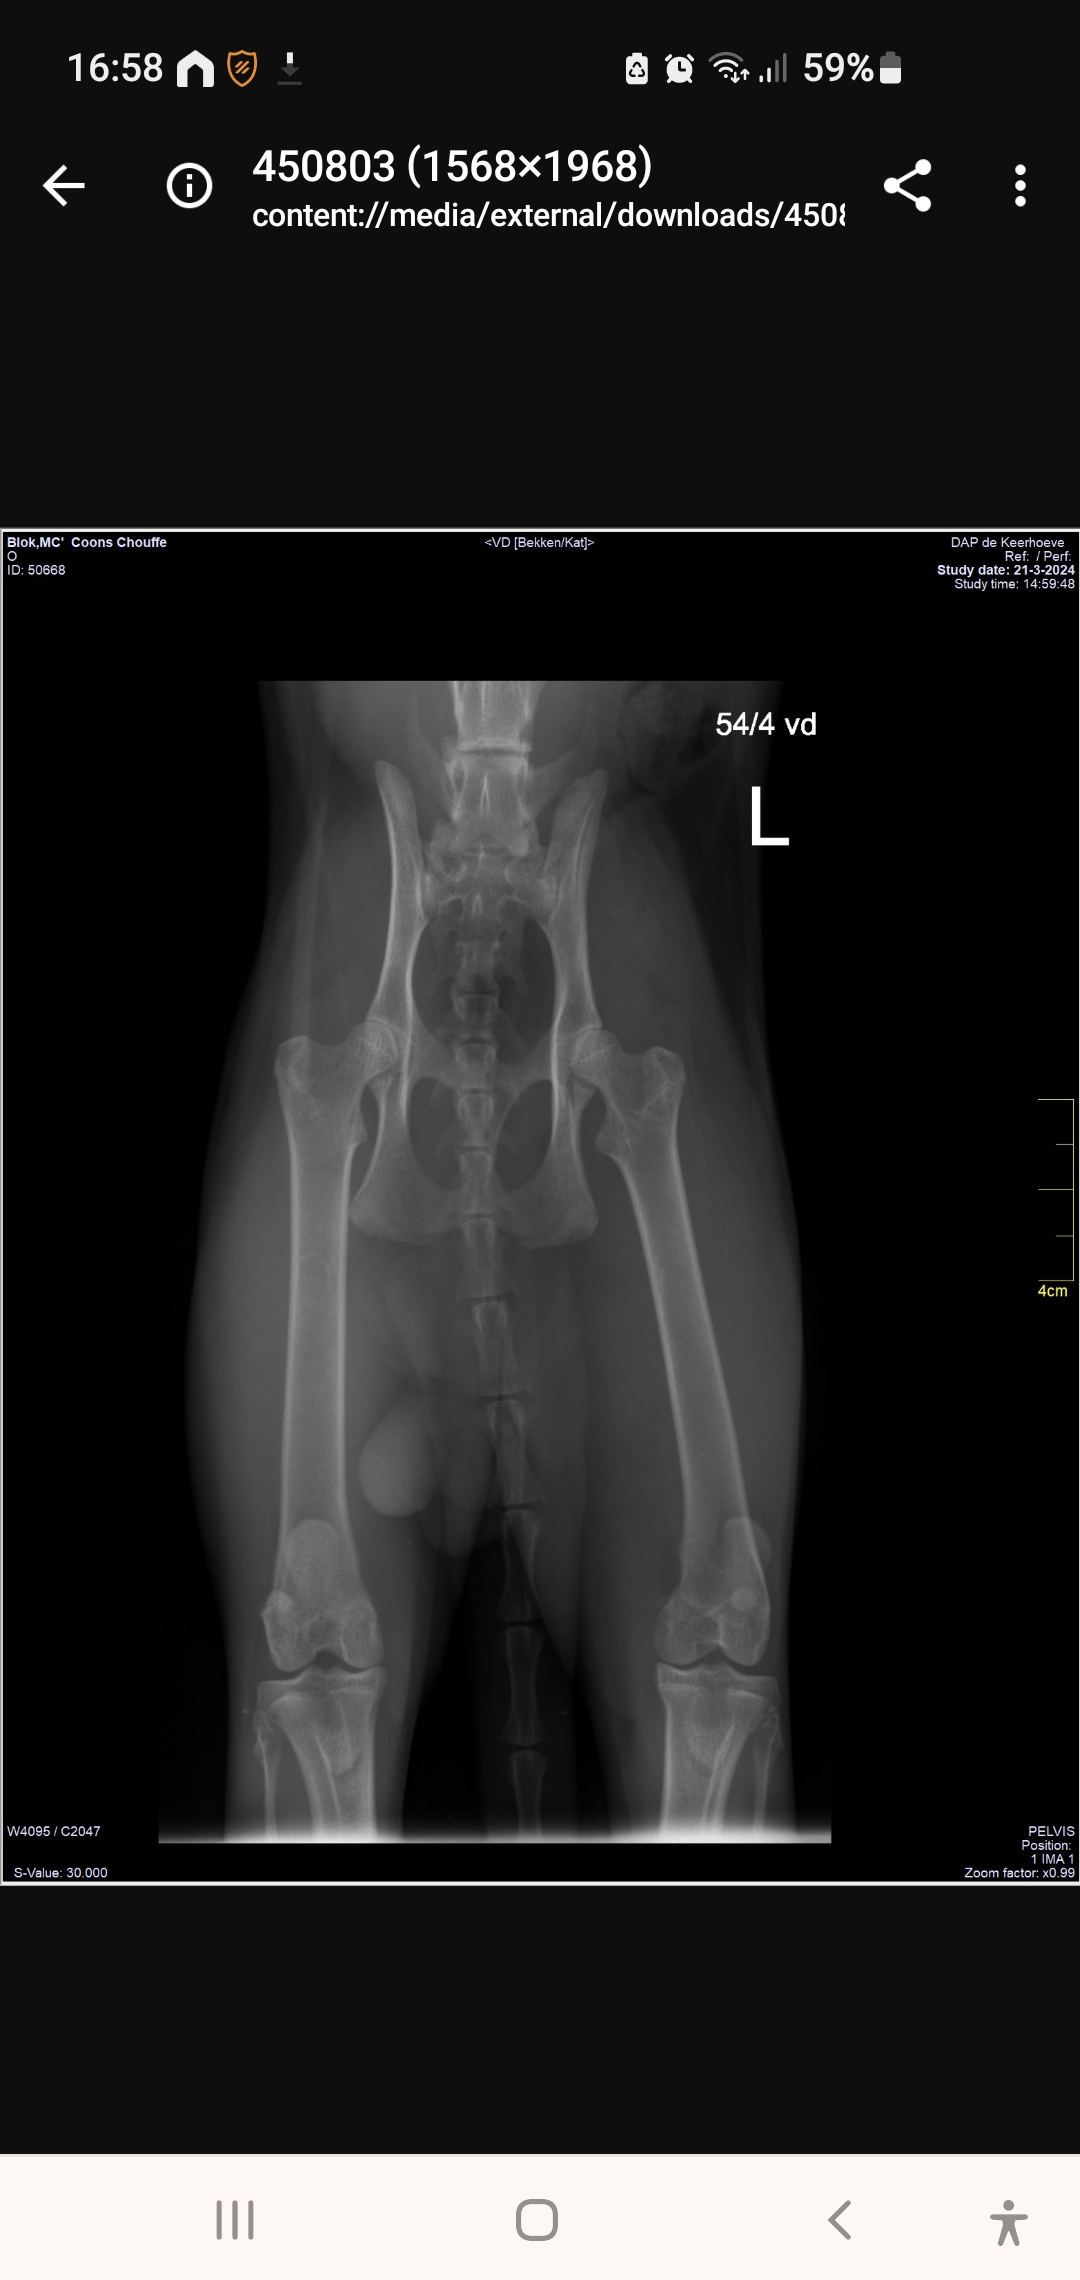

Chouffe Heup Screen π

Afbeelding β 371,1 KB

80 downloads

Download

Screen Check PL Knieen π

Afbeelding β 516,1 KB

72 downloads